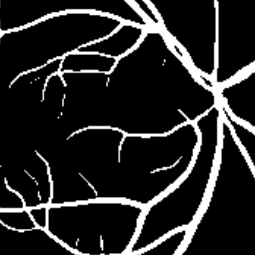

Semantic segmentation of blood vessels is an important task in medical image analysis, but its progress is often hindered by the scarcity of large annotated datasets and the poor generalization of models across different imaging modalities. A key aspect is the tendency of Convolutional Neural Networks (CNNs) to learn texture-based features, which limits their performance when applied to new domains with different visual characteristics. We hypothesize that leveraging geometric priors of vessel shapes, such as their tubular and branching nature, can lead to more robust and data-efficient models. To investigate this, we introduce VessShape, a methodology for generating large-scale 2D synthetic datasets designed to instill a shape bias in segmentation models. VessShape images contain procedurally generated tubular geometries combined with a wide variety of foreground and background textures, encouraging models to learn shape cues rather than textures. We demonstrate that a model pre-trained on VessShape images achieves strong few-shot segmentation performance on two real-world datasets from different domains, requiring only four to ten samples for fine-tuning. Furthermore, the model exhibits notable zero-shot capabilities, effectively segmenting vessels in unseen domains without any target-specific training. Our results indicate that pre-training with a strong shape bias can be an effective strategy to overcome data scarcity and improve model generalization in blood vessel segmentation.